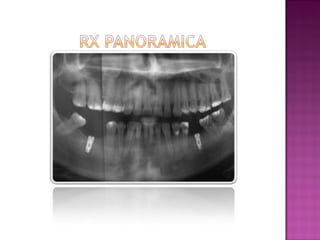

Imagen panorámica Inferior Implantes

Imagen Segmento Inferior Implantes 36 y 46